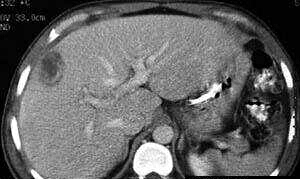

患者以高热,寒战入院,无其他明显症状,行肺CT扫描提示肝脏低密度灶随行腹部增强,发现肝脓肿脓腔形成伴多发间隔,多发子灶,怎么处理?

病例点评: 阿米巴肝脓肿系阿米巴原虫穿过肠壁,经门静脉至肝,在肝内门静脉末梢支拴塞、缺血,同时产生溶组织酶导致细胞坏死而形成的肝脓肿。脓腔较大,多单发,右叶较多。本病多发生在热带或亚热带,在我国不如化脓性肝脓肿多见。CT扫描表现为类圆形低密度区。脓腔内密度不均匀,与坏死程度有关。边缘比较清楚,周围的肉芽组织有增强效应。增强后可为等密度以致病灶缩小。